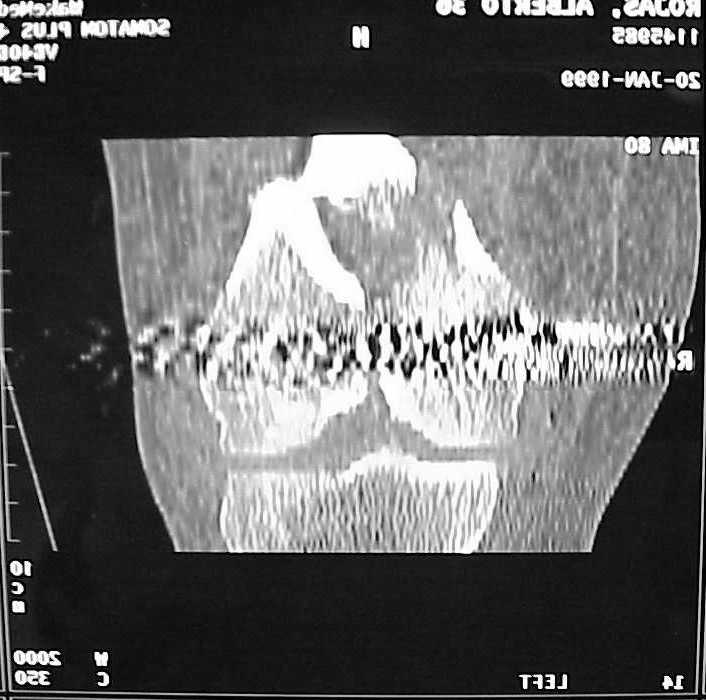

A CT and knee xrays would help identify lateral condyle comminution and/or a "hoffa fragment" of the posterior condyle. I am concerned that the lateral cortex is not sufficient to give purchase for a retrograde IMN. blocking screws could improve this as a possibility. A long blade or LISS if avaible would be my secondary choices. Good luck. Any chance you can get these cases transferred earlier when it

See attached case that was done several years ago before LISS. He had comminuted trochlea and anterior blocking screws were used to prevent anterior IMN cut-out.

place one anterior to where IMN will go if anterior cortex if insufficient and AP screws on either side of the IMN out of the trochlea to provide some additional varus/valgus stability. I worry about the leg going into valgus w/the lack of lateral cortex.